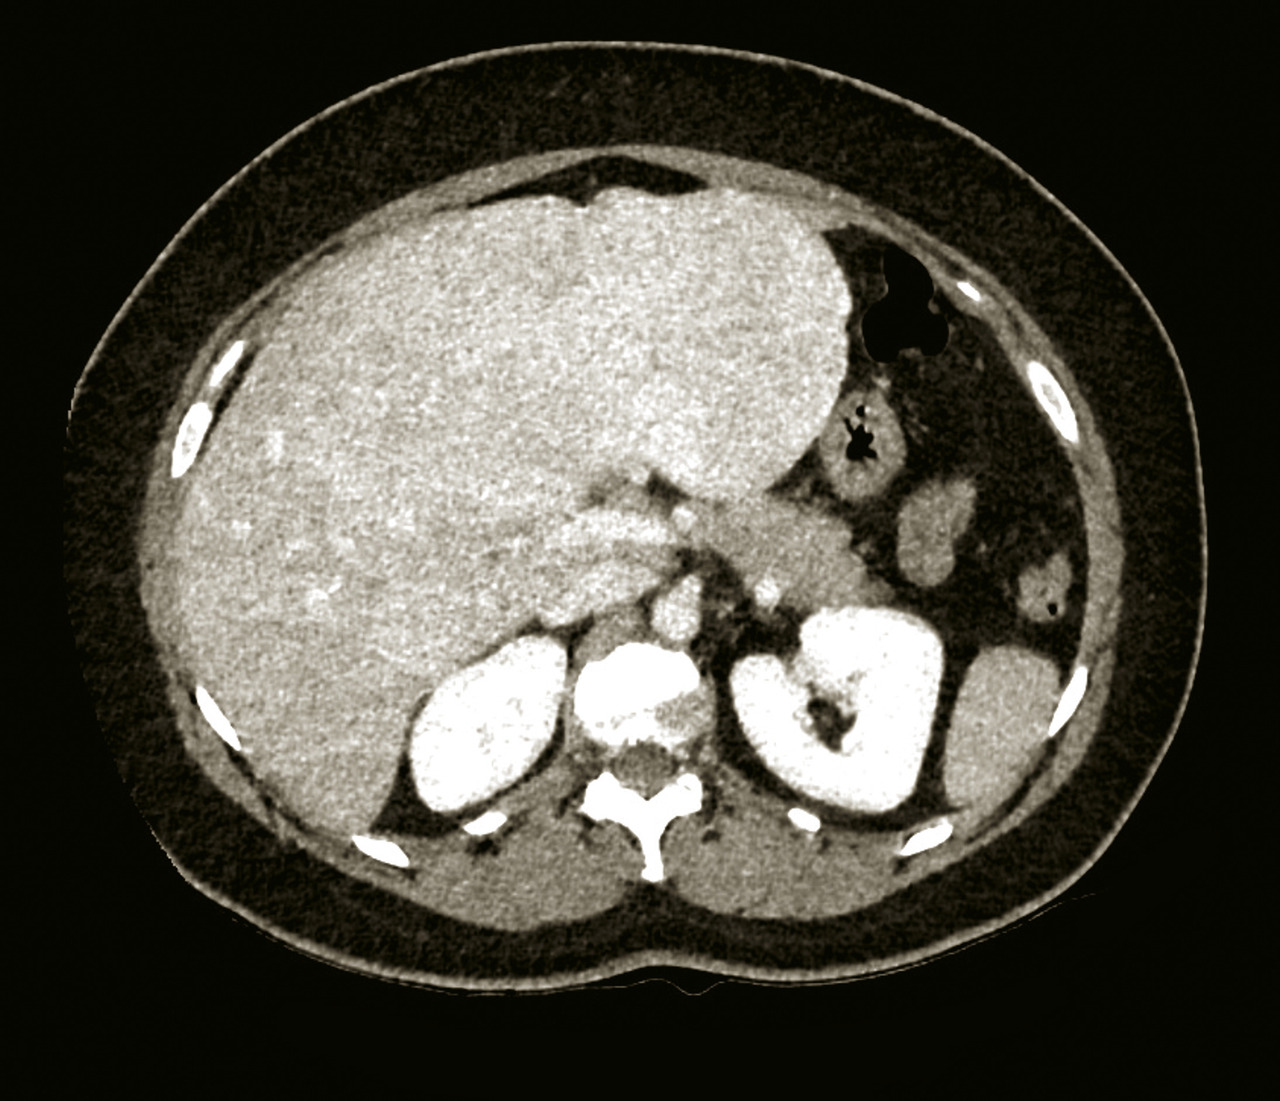

Une imagerie en coupe, tomodensitométrie (TDM) ou imagerie par résonance magnétique (IRM), avec étude triphasique (temps artériel, portal et tardif) après injection de produit de contraste, peut être utile au diagnostic étiologique d’une hépatomégalie.

◗ Donner les caractéristiques du carcinome hépatocellulaire en imagerie injectée : aspect hypervasculaire au temps artériel (phénomène de wash-in), et hypovasculaire au temps portal ou tardif (phénomène de wash-out) par rapport au parenchyme hépatique adjacent.